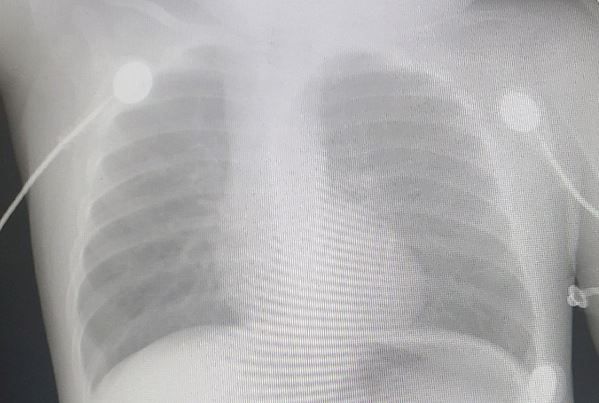

History of present illness. A 10-month-old girl with no medical history of note is brought to the emergency department for dyspnea after choking on a popcorn kernel. According to the mom, initially the child turned blue and lethargic and so mom quickly performed a back blow maneuver and the child improved significantly but has remained out of breath and inconsolable. Prior to the event the child was in normal health and had no recent illness.

Vital signs and physical examination. Pulse oximeter reading is 90%; the child is tachypneic and crying loudly with possible grunting (hard to tell with all the crying) but breath sounds are symmetric.

Initial diagnostic testing. Chest X-ray